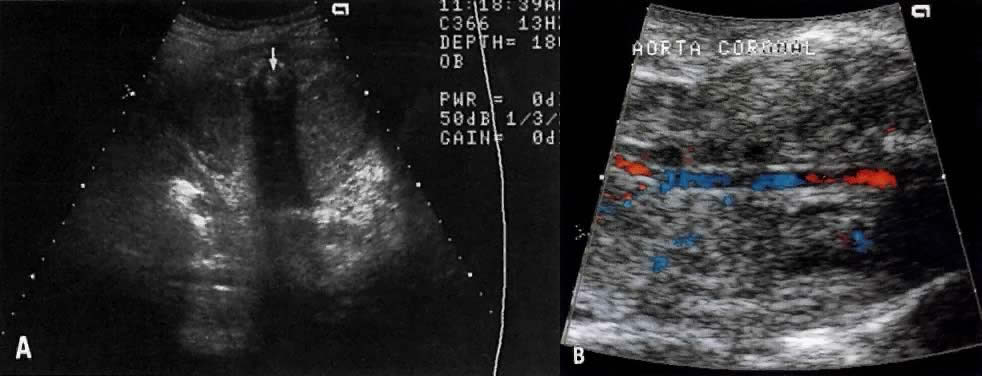

Renal Agenesis

The frequency of this condition is 1:4000 births, and the risk of recurrence is 3%.51 The etiology is variable and may include chromosomal or genetic disorders (recessive or dominant mode of inheritance). It may also be part of the VATER association: vertebral defects, anal atresia, tracheoesophageal fistula, and radial and renal dysplasia. The outcome of fetuses with renal agenesis is poor because of oligohydramnios and associated pulmonary hypoplasia.

Intravenous administration of furosemide (40 mg IV) has not been helpful in differentiating renal agenesis from severe intrauterine growth restriction. Further, because of associated oligohydramnios as well as an enlarged adrenal gland that mimics renal appearance, the diagnosis by gray scale ultrasound is difficult (sensitivity, 50%).51 In suspected cases, however, the use of color Doppler velocimetry may show absence of renal arteries in bilateral renal agenesis and only one renal artery in the unilateral form of this abnormality (Fig. 17).52

Fig. 17. A. Cross-section of fetal abdomen at level of kidneys (spine anterior, arrow) shows both kidneys. The areas on each side of the spine are filled with a uniform echopattern, and no kidneys are seen. B. Color Doppler of aorta in a fetus with renal agenesis fails to outline renal arteries.